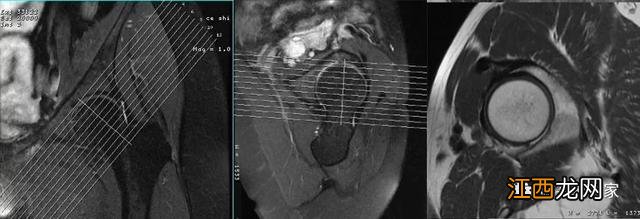

在单髋的斜冠状面和斜矢状面上定位线垂直于股骨颈可以得到单髋短轴面图像,男性髋骨x线示意图,该横断面图像是对斜矢状面和冠状面的补充 。

在单髋的横断面常采用不压脂构造的PDWI扫描 。

相位编码方向为前后方向 。

采用较短TE值,短回波链的高分辨率扫描更有利于显示髋骨关节软骨、盂唇结构 。

采用过采集技术,右侧髋骨图片,防止卷折伪影 。

不压脂的PDWI序列可以将高信号的骨髓和低信号的盂唇清晰分开,可以更好的评估髋臼、股骨近端骨质、髋臼过度覆盖以及髋臼发育不良等 。